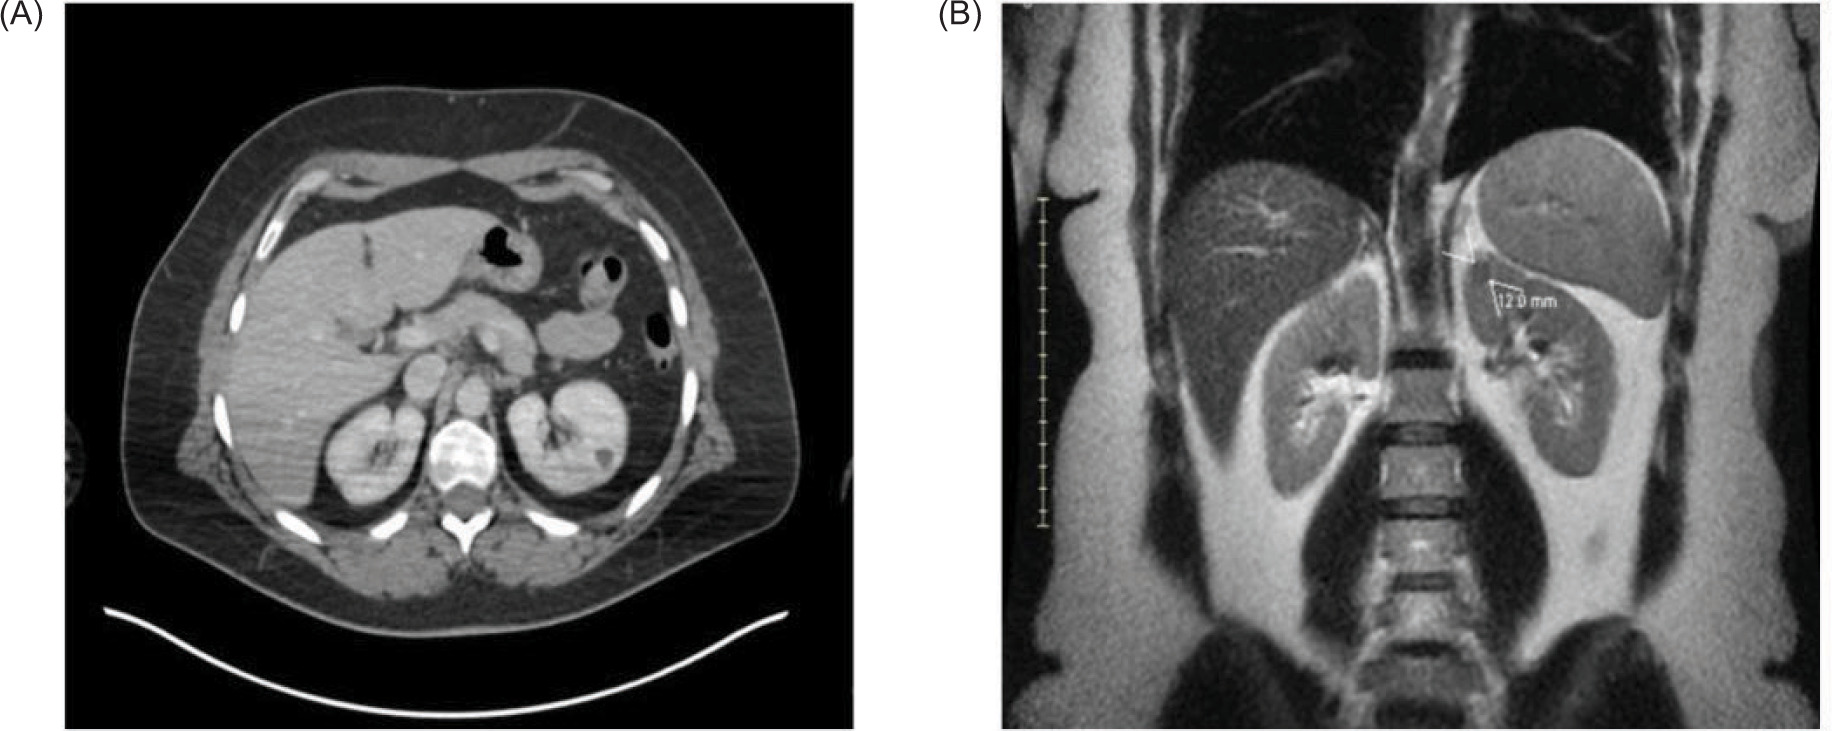

The patient was initially diagnosed with a tumor of the choroid of the right eye, identified pathologically by immunohistochemistry as malignant melanoma. MRI of the abdomen at the time of diagnosis showed the liver, kidneys, and adrenals were within normal limits. The patient was treated with plaque brachytherapy, 21 seeds and an 18 mm plaque left in for 4 days. The patient remained in remission for 9 years until the detection of a 1.5 cm soft tissue nodule in the anterior upper pole of the left kidney on routine surveillance imaging. The patient presented with no symptoms, no hematuria, flank pain, or weight loss. Whole body PET-CT scan showed no other suspicious lesions, and physical exam revealed no cutaneous lesions. Recurrence of melanoma to the left kidney was confirmed, and renal cell carcinoma (RCC) was ruled out by percutaneous renal mass biopsy (Figure 1). After consultation with urology and surgical departments, and medical oncology, the decision was made to pursue surgical removal of this solitary melanoma metastasis. The tumor was of low complexity, with a RENAL score of 6 (R1 E3 N1 L1), for which AUA guidelines indicate PN to be appropriate (19). The patient underwent robotic partial nephrectomy with final pathology confirming melanoma with immunochemistry positive for SOX-10 (20). PN had the same level of difficulty as a nonmelanoma renal mass of similar size. The operative time was 2.5 h, and the length of hospital stay was 3 days. To date, the patient has been monitored with serial imaging every 6 months. No adjuvant systemic therapy was given post-nephrectomy, as the patient had no other evidence of disease at that time, and systemic options for ocular melanoma are limited.

Figure 1: Small renal mass in the upper pole of the left kidney as seen on CT and MRI. (A) Axial view from CT demonstrates a 12 mm lesion. (B) Coronal view from the abdominal MRI also shows a solitary 12 mm upper pole anterior endophytic lesion of the left kidney. Pathology indicates metastatic ocular melanoma.